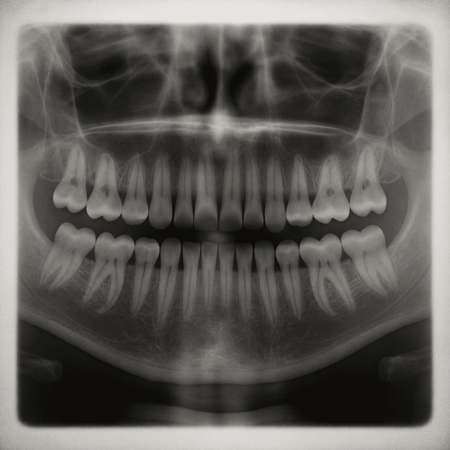

Investigadores del Hospital Kitano en Osaka, Japón, y de la Universidad de Kioto, han comenzado a probar en humanos un fármaco experimental capaz de regenerar dientes pedidos. Los científicos esperan que este medicamento ofrezca una alternativa a las dentaduras postizas y los implantes, y que esté disponible para su uso general a más tardar en 2030.

Como explica Dentistry Today, al inhibir la proteína que produce el gen USAG-1, el cuerpo “recuerda” que tiene la capacidad de generar nuevas piezas dentales. Takahashi explica que los humanos conservamos una tercera generación de dientes en forma de yemas, que normalmente permanecen inactivas. En personas que padecen hiperdoncia, esa capacidad se activa de forma natural.

Dentalx Ray

En 2024, el tratamiento comenzó a probarse en 30 hombres de entre 30 y 64 años que perdieron al menos un diente. A cada uno se le administró el medicamento de manera intravenosa, y el seguimiento durará 11 meses para evaluar su seguridad y efectividad. Hasta ahora, los experimentos previos en animales no han mostrado efectos secundarios, lo que llena de optimismo a los investigadores.